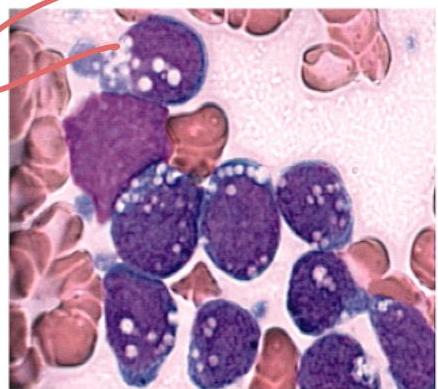

Acute Lymphoblastic Leukemia (ALL)

Scenario: 4 year old boy with fever, spontaneous nose bleeding, hepatosplenomegaly. Peripheral blood smear shown.

Abnormality in peripheral smear? Blast cells (lymphoblasts).

Diagnosis? Acute Lymphoblastic Leukemia (ALL).

Confirmatory Investigations:

- Bone marrow aspiration and biopsy

- Immunohistochemistry

Clinical signs?

- Anemia signs: dizziness, pallor

- Thrombocytopenia: petechiae, purpura

- Recurrent infections

- Bone pain

- Weight loss

- Hepatosplenomegaly

Bone Marrow:

- Single cell blast

Prognosis?

- Good prognosis if treated — children are cured in 90%

- Males treated for 3 years, females treated for 2 years

Treatment:

- Chemotherapy

- Supportive measures

History taking: complaint of pallor + rash.

AML (Acute Myeloid Leukemia): Diagnosed via Bone Marrow aspirate/biopsy.